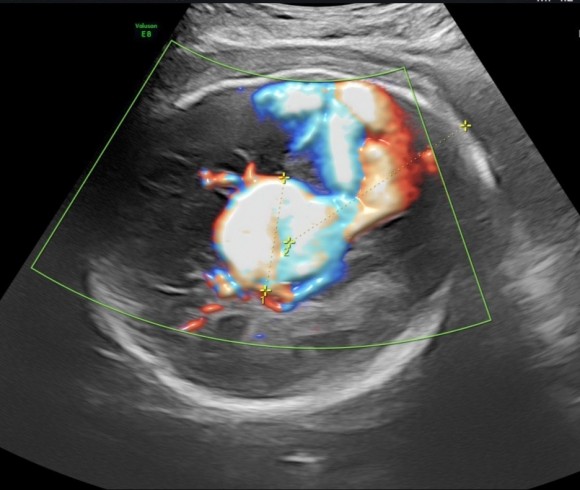

Аневризма вены Галена – это изменение сосудов головного мозга. Опасная патология, которая грозит кровоизлиянием. Порок формируется до рождения ребенка. Из-за расширения вены Галена, которая забирает кровь из глубинных отделов полушарий мозга, возникает риск ее разрыва.

— Она наблюдалась у нас в НИИ ОММ. В 30 недель у плода была выявлена аневризма вены Галена. Этот порок развития, он коварен тем, что поздно возникает – это диагноз третьего триместра беременности. Он был поставлен, когда пациентка пришла на очередной осмотр, в 31 неделю, после УЗИ.

Это достаточно тяжелый порок. Такие дети погибают либо внутриутробно, либо после рождения. Надо было прерывать беременность, но женщина отказалась. Сосудистый шар достиг в диаметре 36 мм. Это, фактически, половина головки плода на таком сроке, все это осложнялось гидроцефалией или водянкой головного мозга. То есть прогноз был крайне неблагоприятный.

— Мамочка чувствует себя хорошо. Плод мы смотрим, кровотоки у него хорошие, сердечко не увеличивается, но вот по центральной нервной системе мы пока не можем сказать, как она отреагирует. Ну, обследуем, делаем УЗИ, МРТ. Отслеживаем ситуацию каждую неделю.